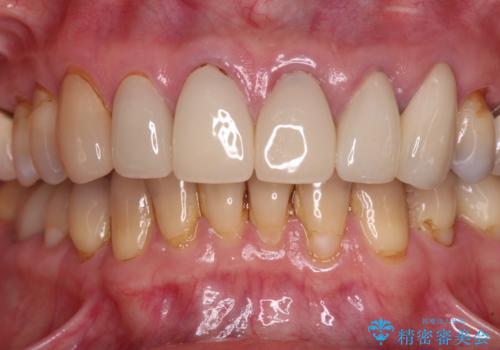

もげてしまった前歯をセラミッククラウンで自然に

- 前歯が土台ごと外れてしまったとのことで来院された患者様です。

土台は外れていましたが破折などの問題はなく、土台からの再治療で対応可能な状態でした。

隣の犬歯も神経が取り除かれていたしたが、ラミネートベニアで治療されており、裏側でむし歯が進行する可能性があったため、こちらも治療が必要と判断されました。

今回の治療を機会に前歯全体をやり直すことも考えたそうですが、取り急ぎ要治療となった2歯を先に治療することとしました。

外れてしまったクラウンを保管しておき、新しいクラウン製作の際に技工所に送ることで、今までと同じような色合いに仕上げることができ、周囲のクラウンとバランスを取ることができます。